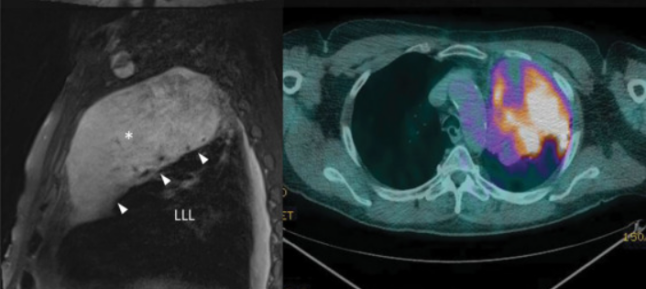

患者,男性,60岁。因嗜肺军团菌肺炎导致急性呼吸衰竭而接受有创机械通气治疗2周,在出院1个月后患者仍有持续性呼吸困难和咳嗽。首次住院时胸部CT见图4,胸片显示左上肺实变。

图4 首次住院时胸部CT

再次入院时胸部CT见图5,检查结果示左下肺实变。

图5 再次入院时胸部CT